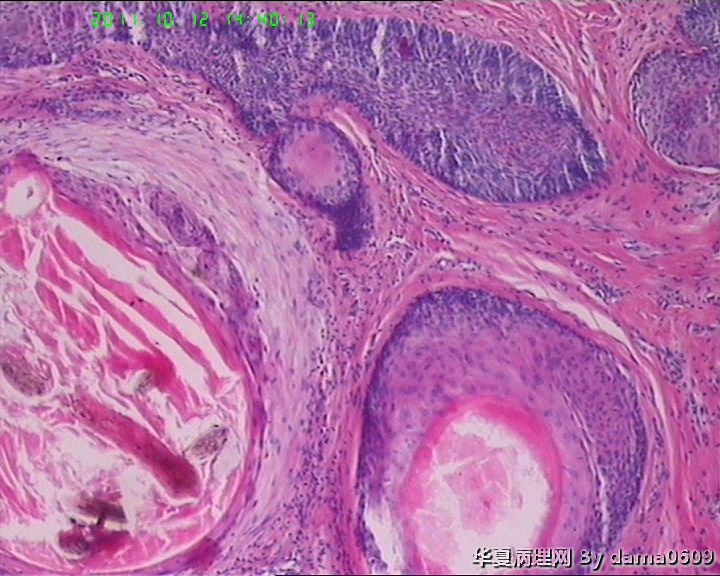

女,42岁,右眼外上方皮下肿物4年。

送检:椭圆形肿物,v:0.5x0.5x0.4cm,实性,灰白色,质软。

毛发腺瘤

毛发上皮瘤

毛鞘瘤。

脂溢性角化病伴局灶钙化及色素沉积.